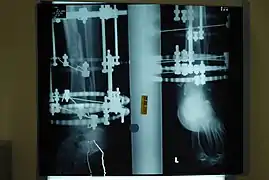

The photographs and radiographs illustrate the application and emplacement of an external fixator, an Ilizarov apparatus, to repair the open fracture of the lower left leg of a man. The photographs were taken four weeks after the patient fractured the shinbone (tibia) and the calfbone (fibula) of his left leg, and two weeks after the surgical emplacement of the Ilizarov apparatus to immobilise the leg and isolate the wound and fracture site to facilitate healing.

X-ray of the open fracture of the left leg; the external fixator was installed ca. 24 hrs. in hospital.

X-ray of the open fracture of the left leg; the external fixator was installed ca. 24 hrs. in hospital. X-ray of the open fracture site immediately after installation of the Ilizarov apparatus.

Superior perspective of the apparatus emplaced into the left leg of the patient. X-ray of the fracture site and the emplaced apparatus, two months post-fracture; perspective 1-4.

X-ray of the fracture site and the emplaced apparatus, two months post-fracture; perspective 1-4. X-ray of the fracture site and the emplaced apparatus, two months post-fracture; perspective 2-4.

X-ray of the fracture site and the emplaced apparatus, two months post-fracture; perspective 2-4. X-ray of the callus forming at the fracture site, three months post-fracture; perspective 3-4.

X-ray of the callus forming at the fracture site, three months post-fracture; perspective 3-4. X-ray of the callus forming around the fracture site, three months post-fracture; perspective 4-4.

X-ray of the callus forming around the fracture site, three months post-fracture; perspective 4-4. X-ray perspectives of the callus-formation progress and healing of the fractured tibia and fibula bones, four months post-fracture.

X-ray perspectives of the callus-formation progress and healing of the fractured tibia and fibula bones, four months post-fracture.